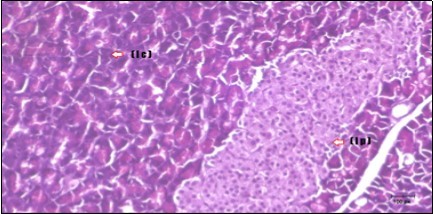

Pancreas Histopathological Observations

Histological examination of pancreas of the control rats showed normal sized islets of pancreas (Ip) compared to the diabetic rats which showed markedly atrophic islets of pancreas (I.p.) (Figure 8 and Figure 9). Pancreas of in groups (3) and (4) rats showed mild atrophic islets of pancreas (I.p.) with inflammatory cellular infiltrate (Figure 10 and Figure 11). The pancreas of rats in group (5) showed nearly normal islets of pancreas (I.p.) with few inflammatory cellular infiltrate (I.c.) (Figure 12).

Figure 12.Photomicrogragh of pancreas section of treated rat with both Fenugreek and Glimepiride showing nearly normal islets of Langerhans with spindle (arrow) & polygonal cells (dashed- arrow). (H&E) (40x).

Histopathological observation in diabetic control showed degenerative changes in both endocrine and exocrine pancreases. A probable explanation may be related to oxidative stress resulting from hyperglycemia which decreases the antioxidants levels and increases ROS 33 and the activities of antioxidant enzyme were altered in diabetic rats. These effects further exacerbate the development and progression of diabetes complications and these may represent the causes of degeneration revealed in histological sections. Fenugreek improved blood glucose levels and insulin, lowered pancreatic islet and β-cells damage which may be attributed to its immune modulatory activity and insulin stimulation action along with its antioxidant potential 32. Glimepiride caused restoration of morphology of beta cell of diabetic and it increased percentage of beta cells 34. This protective effect could be attributed to the antioxidant properties of Glimepiride. Combination therapy improves the protective effect of both therapies alone.